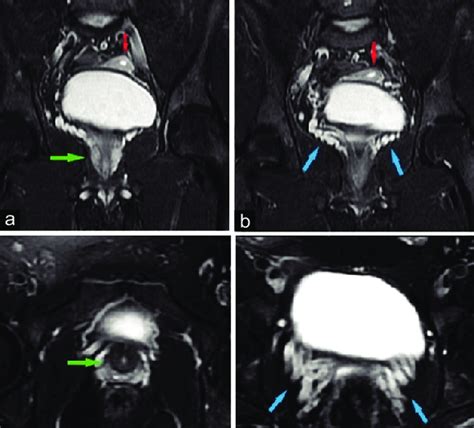

Ovotesticular Disorder Of Sex Development Approach And Management Of An Index Case In The